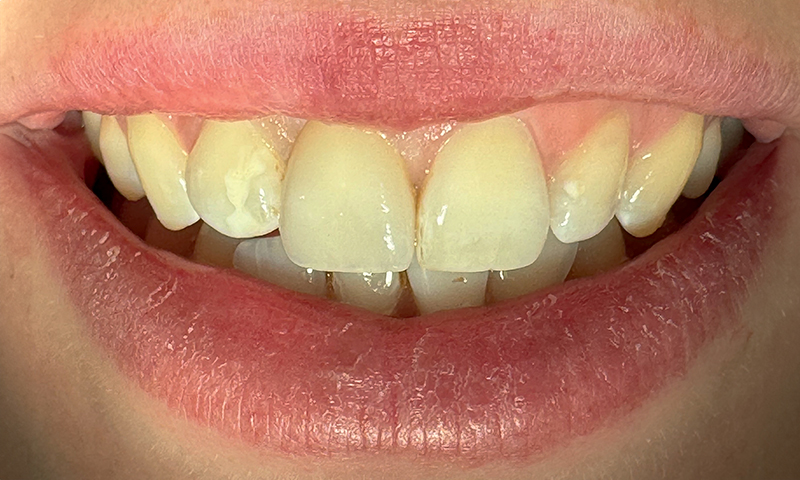

Fig. 16 (caso 3) - Quadro clinico frontale 5 anni dopo l'impianto

Fig. 21 (caso 4) - Visione finale del sorriso dopo 7 anni. Completo recupero dell'estetica e osteointegrazione nonostante la condizione clinica iniziale